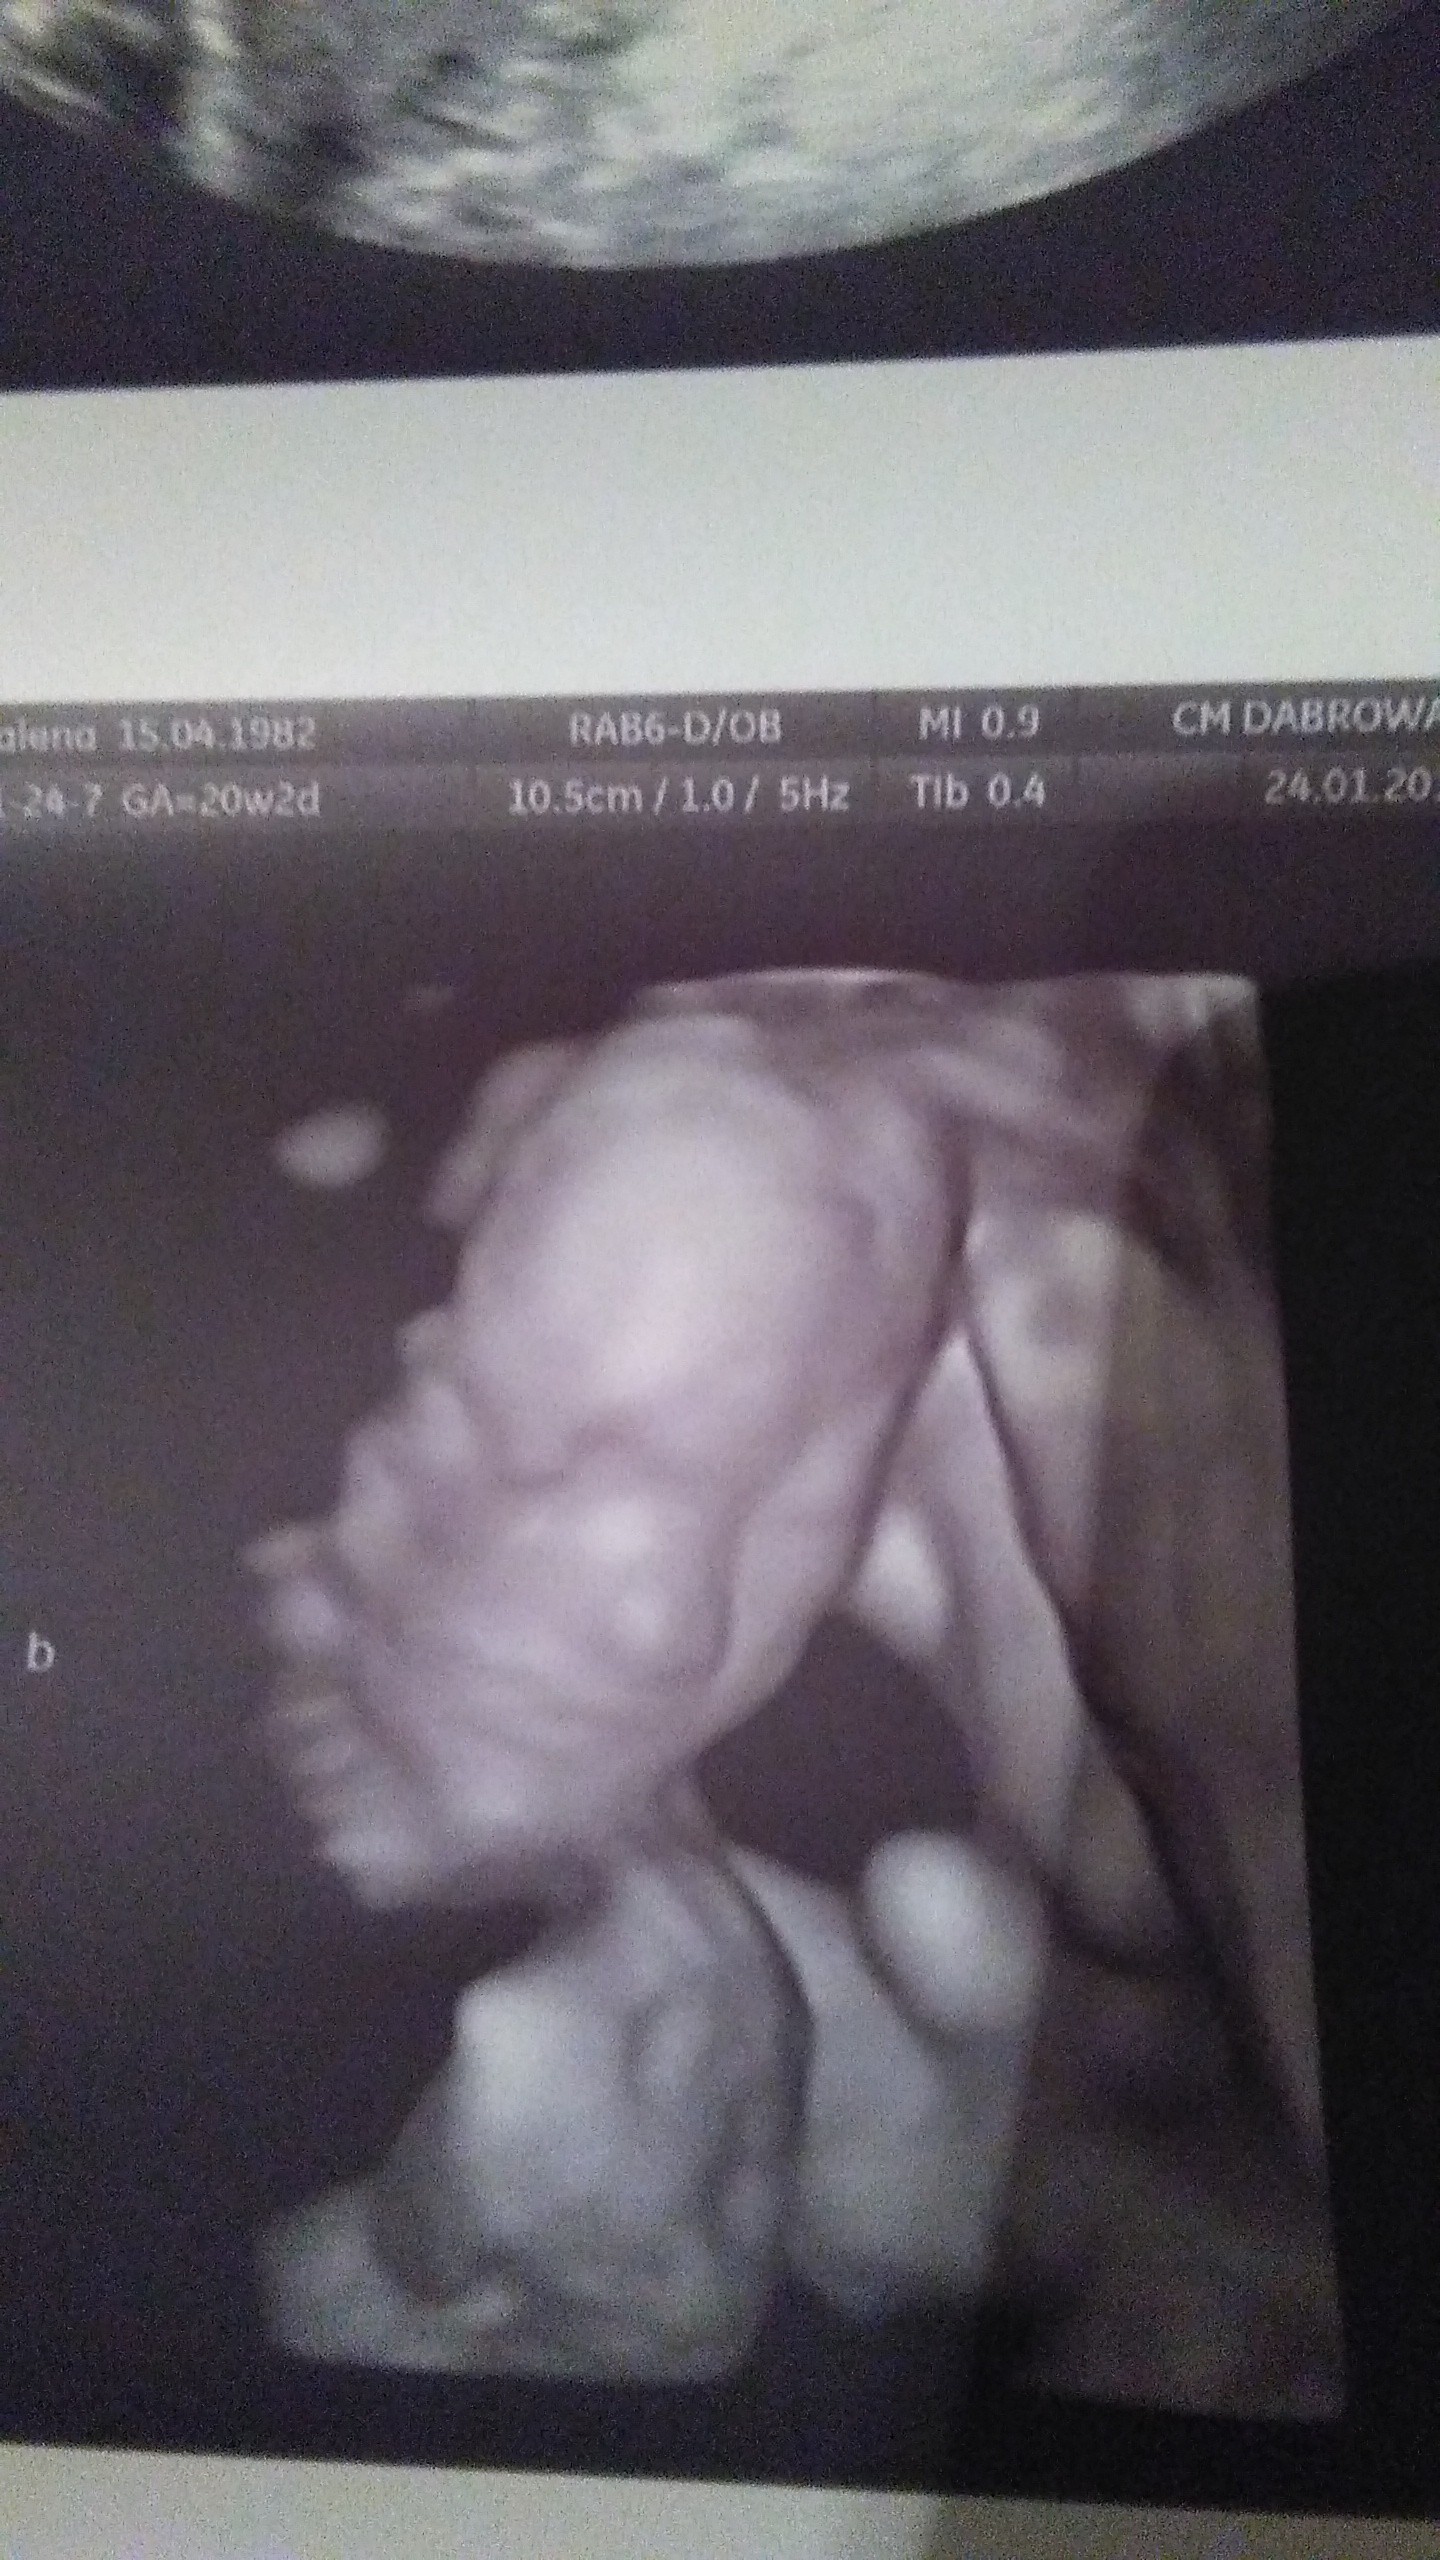

Dziewczyny walczcie dzielnie o swoje marzenia. Jako przykład przedstawiam wam mój mały wielki cud - bliźnięta jednojajowe. 20 tydzień. Trzeci transfer, podana najslabsza blastusia, która w dodatku podzieliła się i oto mamy - Olę i Izę

gratulacje oby więcej takich wiadomośći Marzenia sie spełniająDziewczyny walczcie dzielnie o swoje marzenia. Jako przykład przedstawiam wam mój mały wielki cud - bliźnięta jednojajowe. 20 tydzień. Trzeci transfer, podana najslabsza blastusia, która w dodatku podzieliła się i oto mamy - Olę i Izę